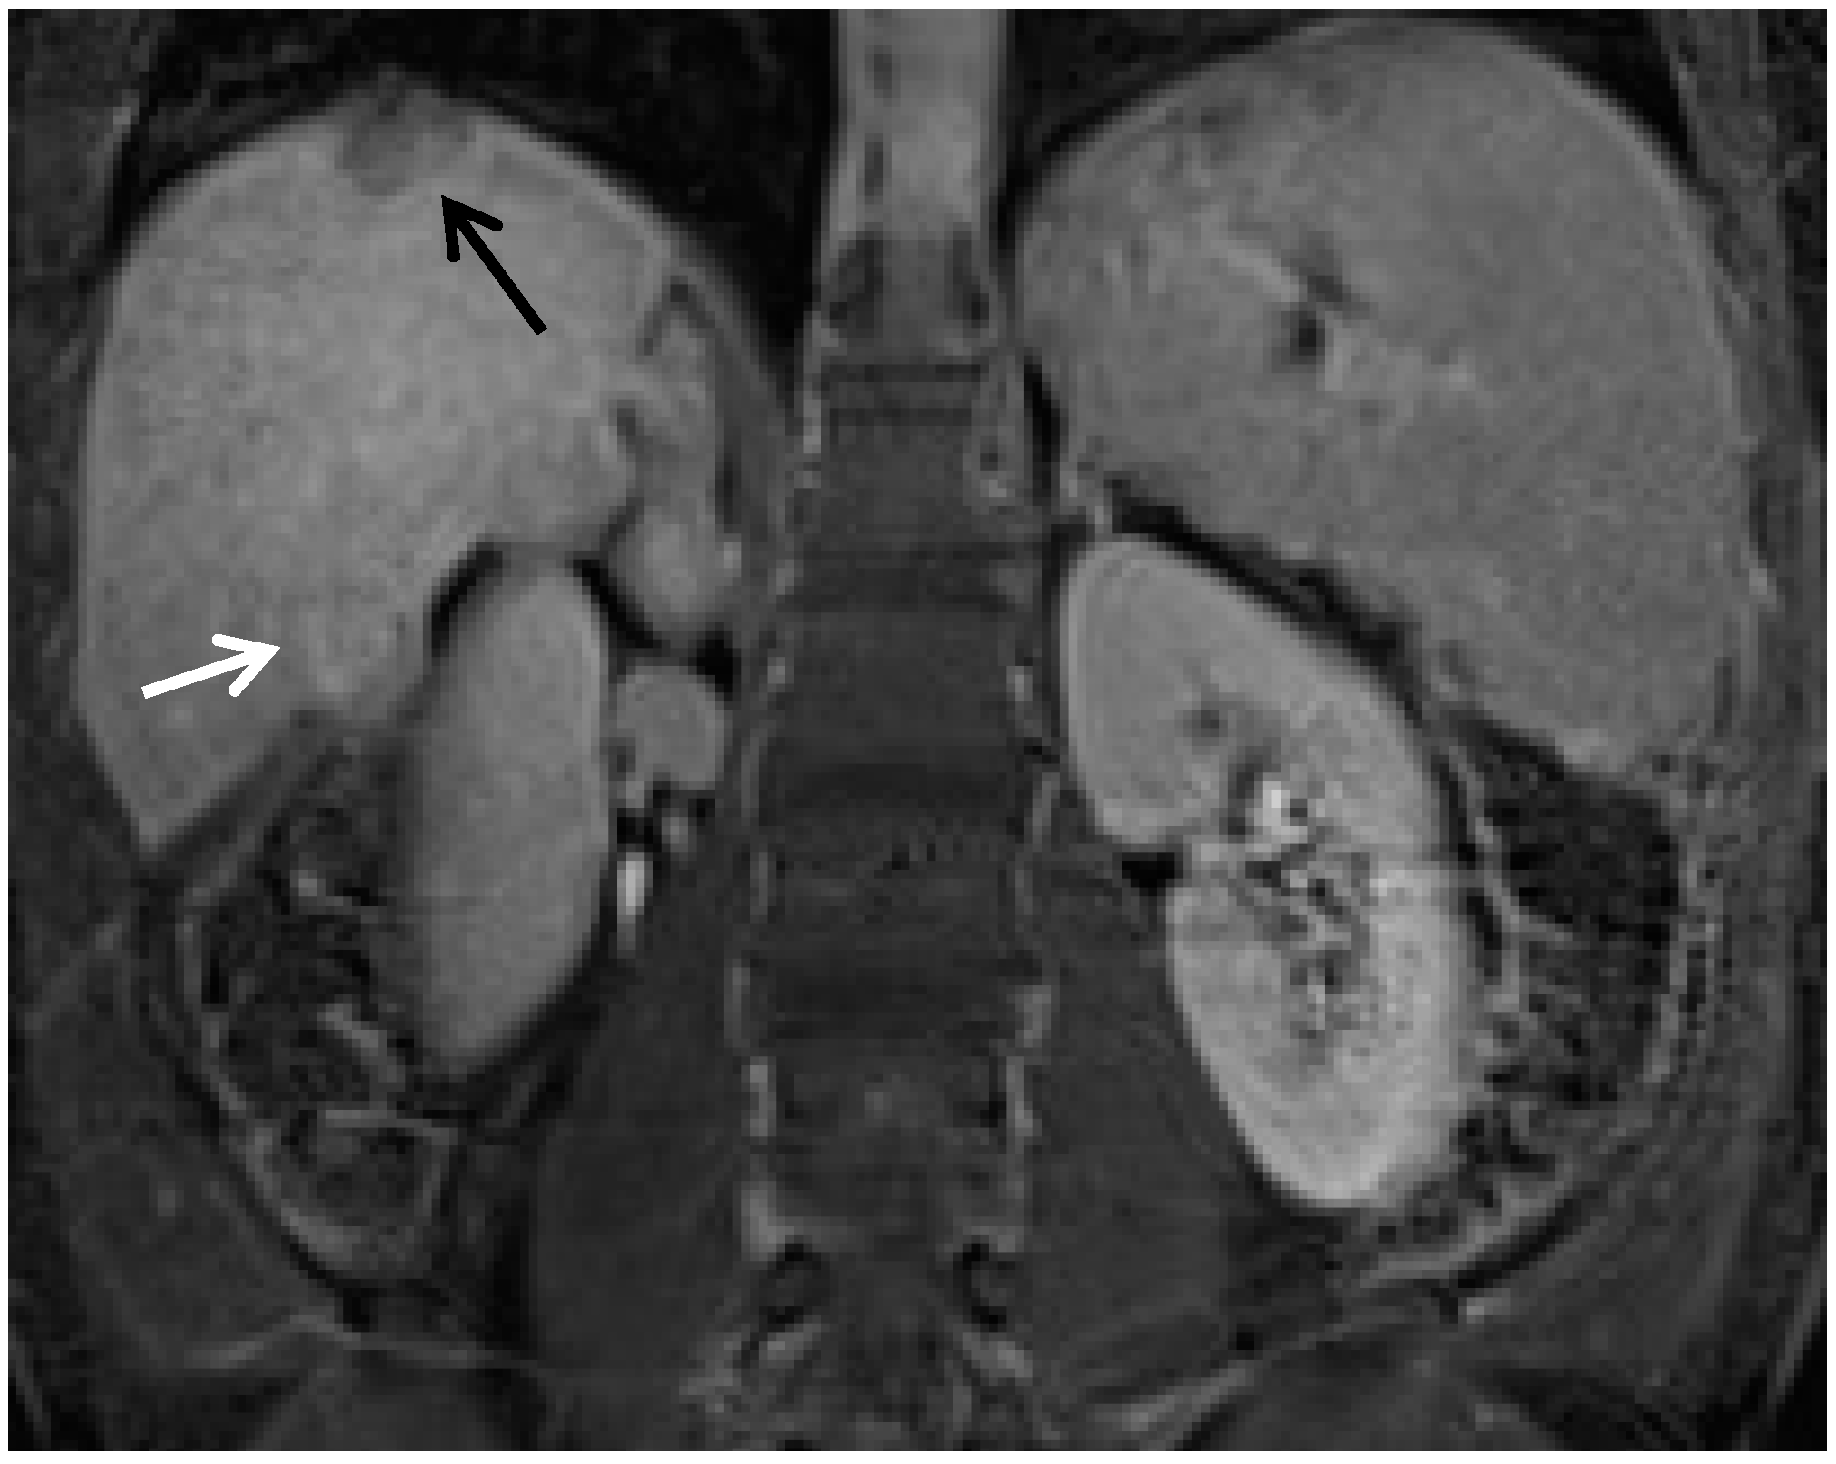

- Motosugi, U.; Bannas, P.; Sano, K.; Reeder, S.B. Hepatobiliary MR contrast agents in hypovascular hepatocellular carcinoma. J. Magn. Reson. Imaging 2015, 41, 251–265. [Google Scholar] [CrossRef] [PubMed]

- Kitao, A.; Matsui, O.; Yoneda, N.; Kozaka, K.; Kobayashi, S.; Koda, W.; Gabata, T.; Yamashita, T.; Kaneko, S.; Nakanuma, Y.; et al. Hypervascular hepatocellular carcinoma: Correlation between biologic features and signal intensity on gadoxetic acid-enhanced MR images. Radiology 2012, 265, 780–789. [Google Scholar] [CrossRef] [PubMed]

- Bashir, M.R.; Gupta, R.T.; Davenport, M.S.; Allen, B.C.; Jaffe, T.A.; Ho, L.M.; Boll, D.T.; Merkle, E.M. Hepatocellular carcinoma in a north american population: Does hepatobiliary MR imaging with Gd-EOB-DTPA improve sensitivity and confidence for diagnosis? J. Magn. Reson. Imaging 2013, 37, 398–406. [Google Scholar] [CrossRef] [PubMed]

- Choi, J.Y.; Lee, J.M.; Sirlin, C.B. CT and MR imaging diagnosis and staging of hepatocellular carcinoma: Part I. Development, growth, and spread: Key pathologic and imaging aspects. Radiology 2014, 272, 635–654. [Google Scholar] [CrossRef] [PubMed]

- Kim, A.Y.; Kim, Y.K.; Lee, M.W.; Park, M.J.; Hwang, J.; Lee, M.H.; Lee, J.W. Detection of hepatocellular carcinoma in gadoxetic acid-enhanced MRI and diffusion-weighted MRI with respect to the severity of liver cirrhosis. Acta Radiol. 2012, 53, 830–838. [Google Scholar] [CrossRef] [PubMed]